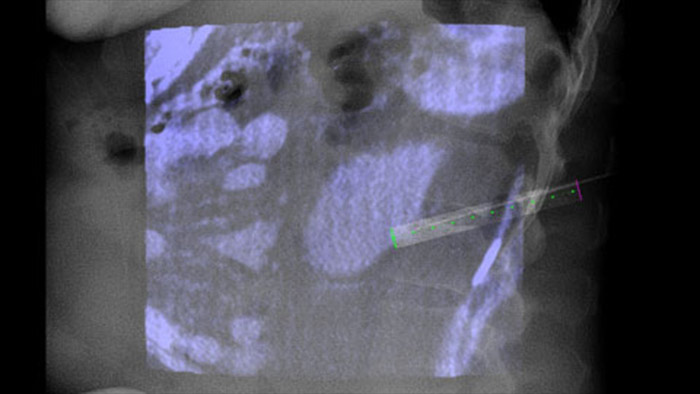

Le double affichage permet de superposer une image 3D avant la procédure (TDM/IRM/TEP-TDM) sur une image CBCT 3D double affichage au cours de la procédure pour mieux visualiser les lésions et accéder aux données critiques pour la planification des aiguilles.

XperGuide fournit un guidage par imagerie en temps réel très précis de chaque aiguille vers une position cible en superposant les trajectoires préplanifiées avec l’imagerie fluoroscopique.3